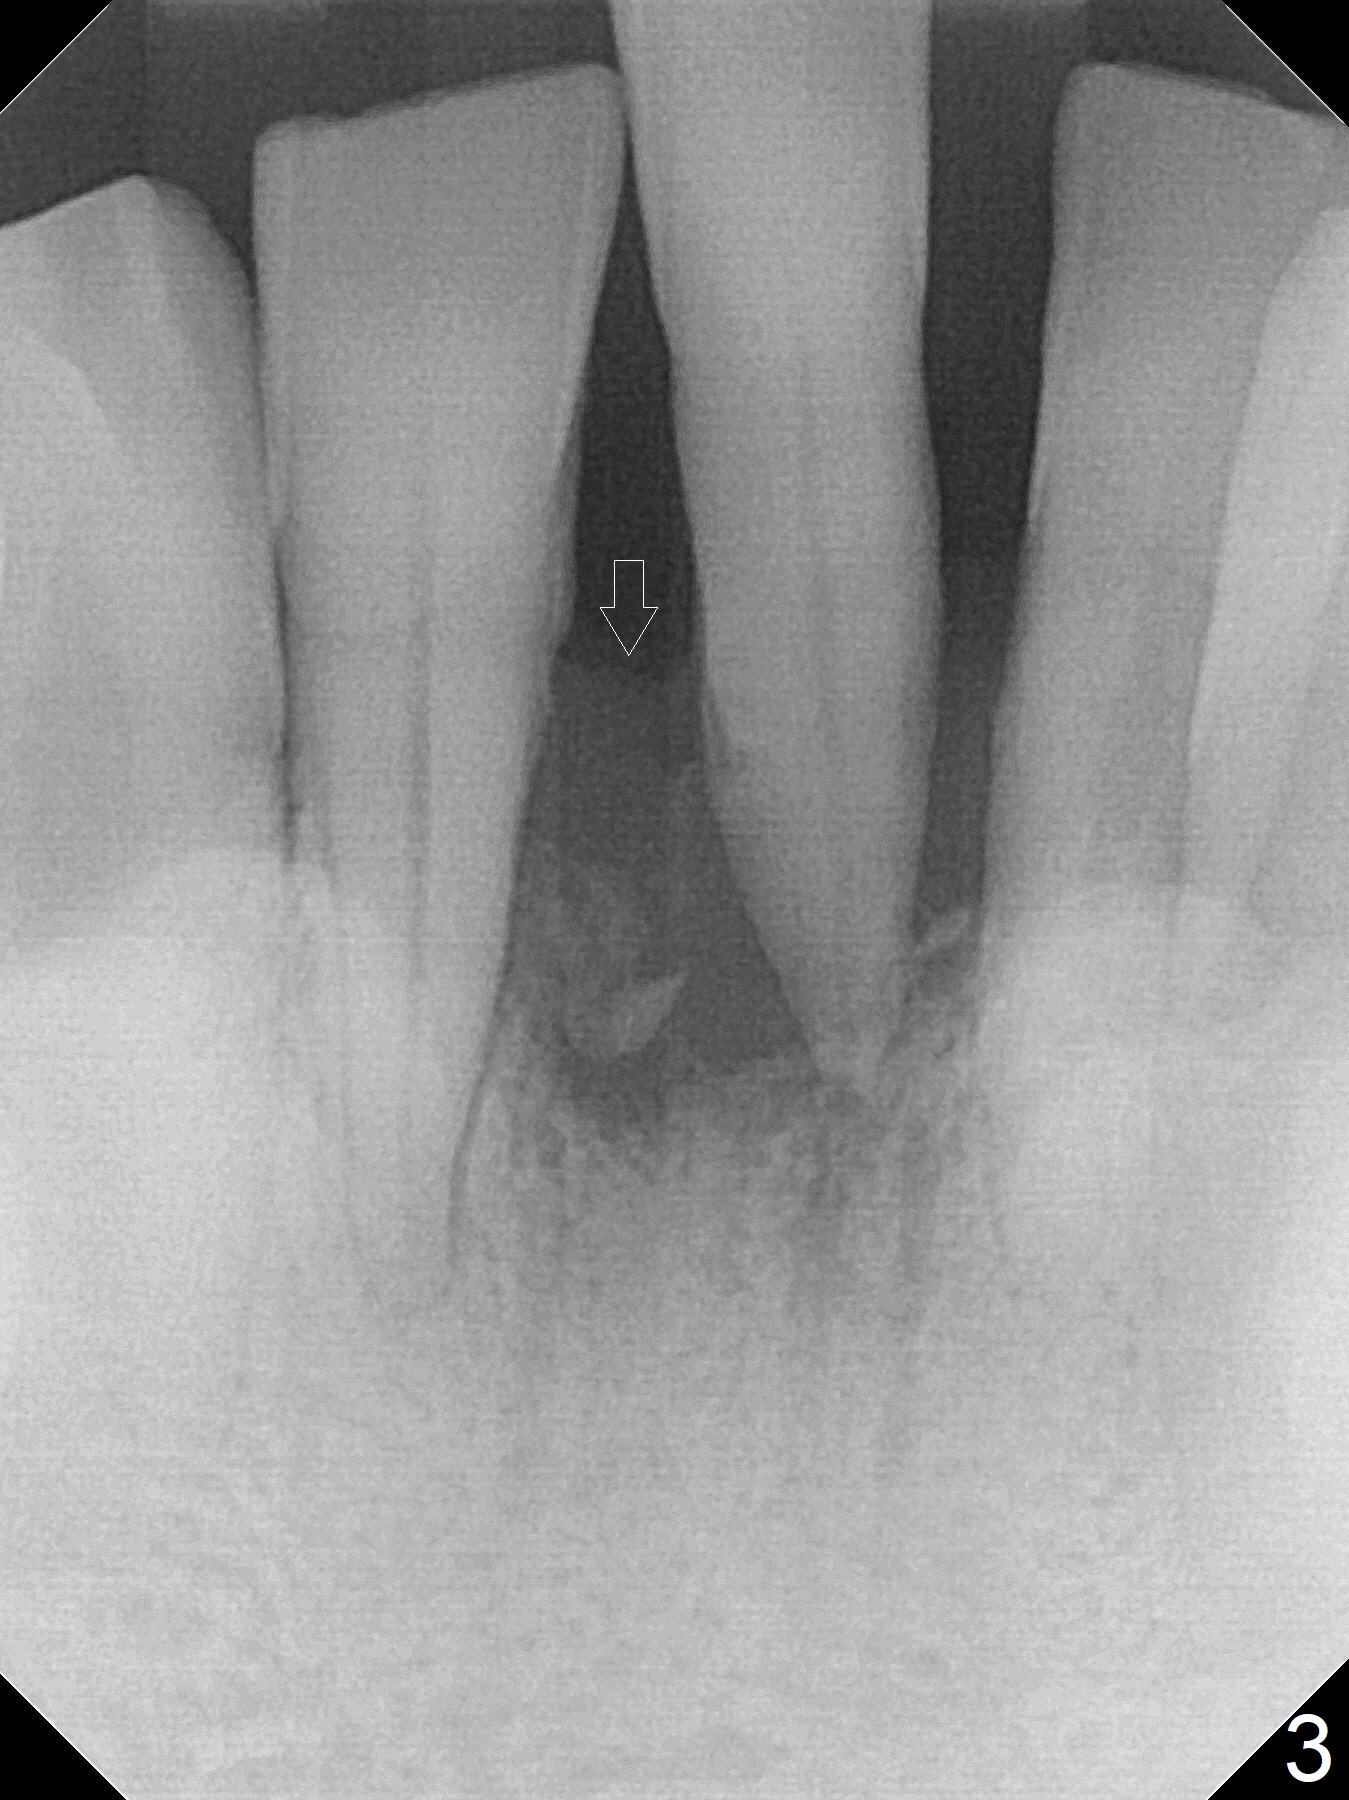

When the patient returns for implant placement 1.5 years after the last treatment (SRP), the tooth #25 has exfoliated, whereas the tooth #24 is severely displaced (Fig.1-3). In fact the buccolingual plates are found to be lost after extraction, corresponding to change in gingival color indicated by an arrowhead in Fig.1. Initial osteotomy with 1.2 mm drill is parallel to the terminal branches of the Incisive Canal (Fig.4 arrowheads). Since the gingiva is as thick as 7.5 mm (Fig.3 arrow), a 3x14 mm 1-piece implant with 4 mm cuff is placed (Fig.5); three implant threads are outside the native bone; with allograft (*) placed and the neighboring crests being coronal to the threads, the chance of periimplantitis should be remote. An immediate provisional is fabricated to contain the graft in place. Meanwhile the tooth #2 is symptomatic with crack. The top 3 threads appear to be contacted by the newly formed crestal bone 6 months postop (Fig.6 *). Bone appears to have grown into the space between implant threads 6 months post cementation (13 months postop).